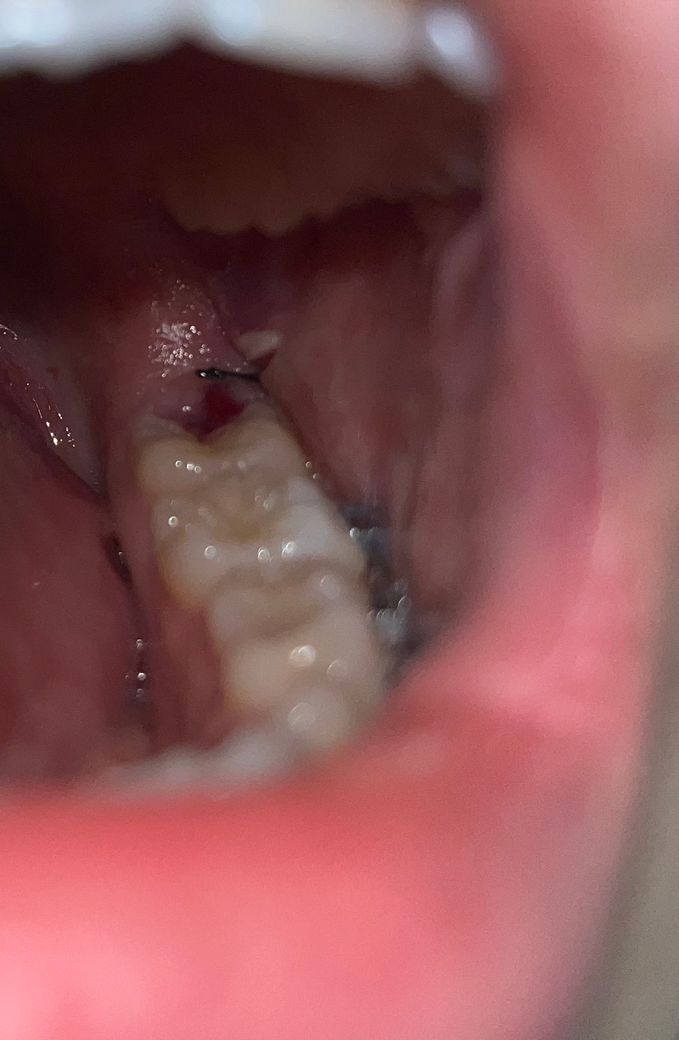

매복 사랑니 발치했는데 저 하얀색은 뭔가요?

매복사랑니를 21일 오후에 뽑았고 어제 소독갔다왔습니다. 아직까지 약간의 통증이 있겠죠? 저 하얀부분은 뭘까요? 드라이소켓은 아니겠죠? 약도 잘챙겨먹고있습니다. 그리고 피가 저쪽에 고여? 굳어? 있는데 혈병일까요? 잘나아가고있는걸까요ㅠㅠ

하얀색은 정상적인 잇몸 회복 과정 중에서도 나타나기 때문에 증상이 없다면 괜찮을 겁니다.

하얀색은 잇몸이 치유되면서 생기는 자연스러운 현상입니다. 통증은 아직 잇몸이 아물지 않아서 그럴수 있습니다.

하얀색은 염증육아조직 등으로 보이나 드라이소켓의 양상은 아닙니다